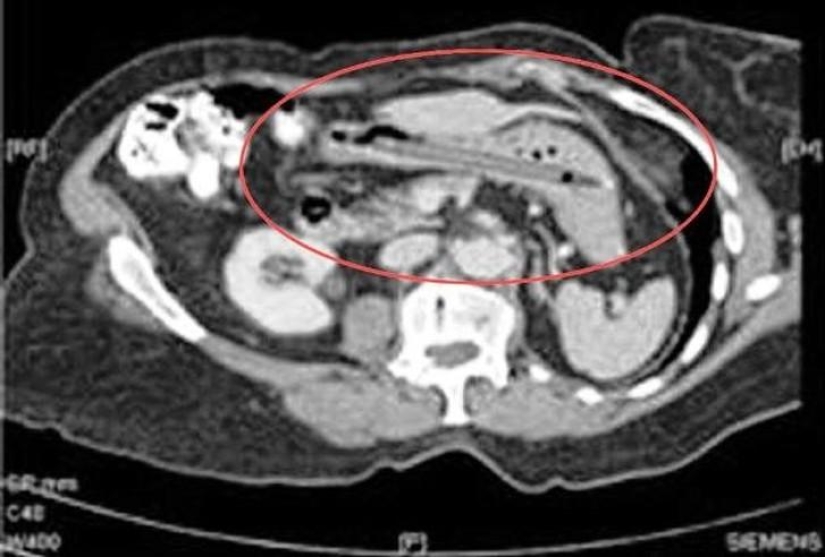

23. Metanfetaminas.